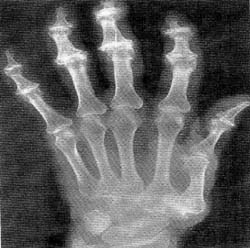

<Á¤»ó

°ñ ±¸Á¶> <°ñ´Ù°øÁõÀÇ

°ñ ±¸Á¶>